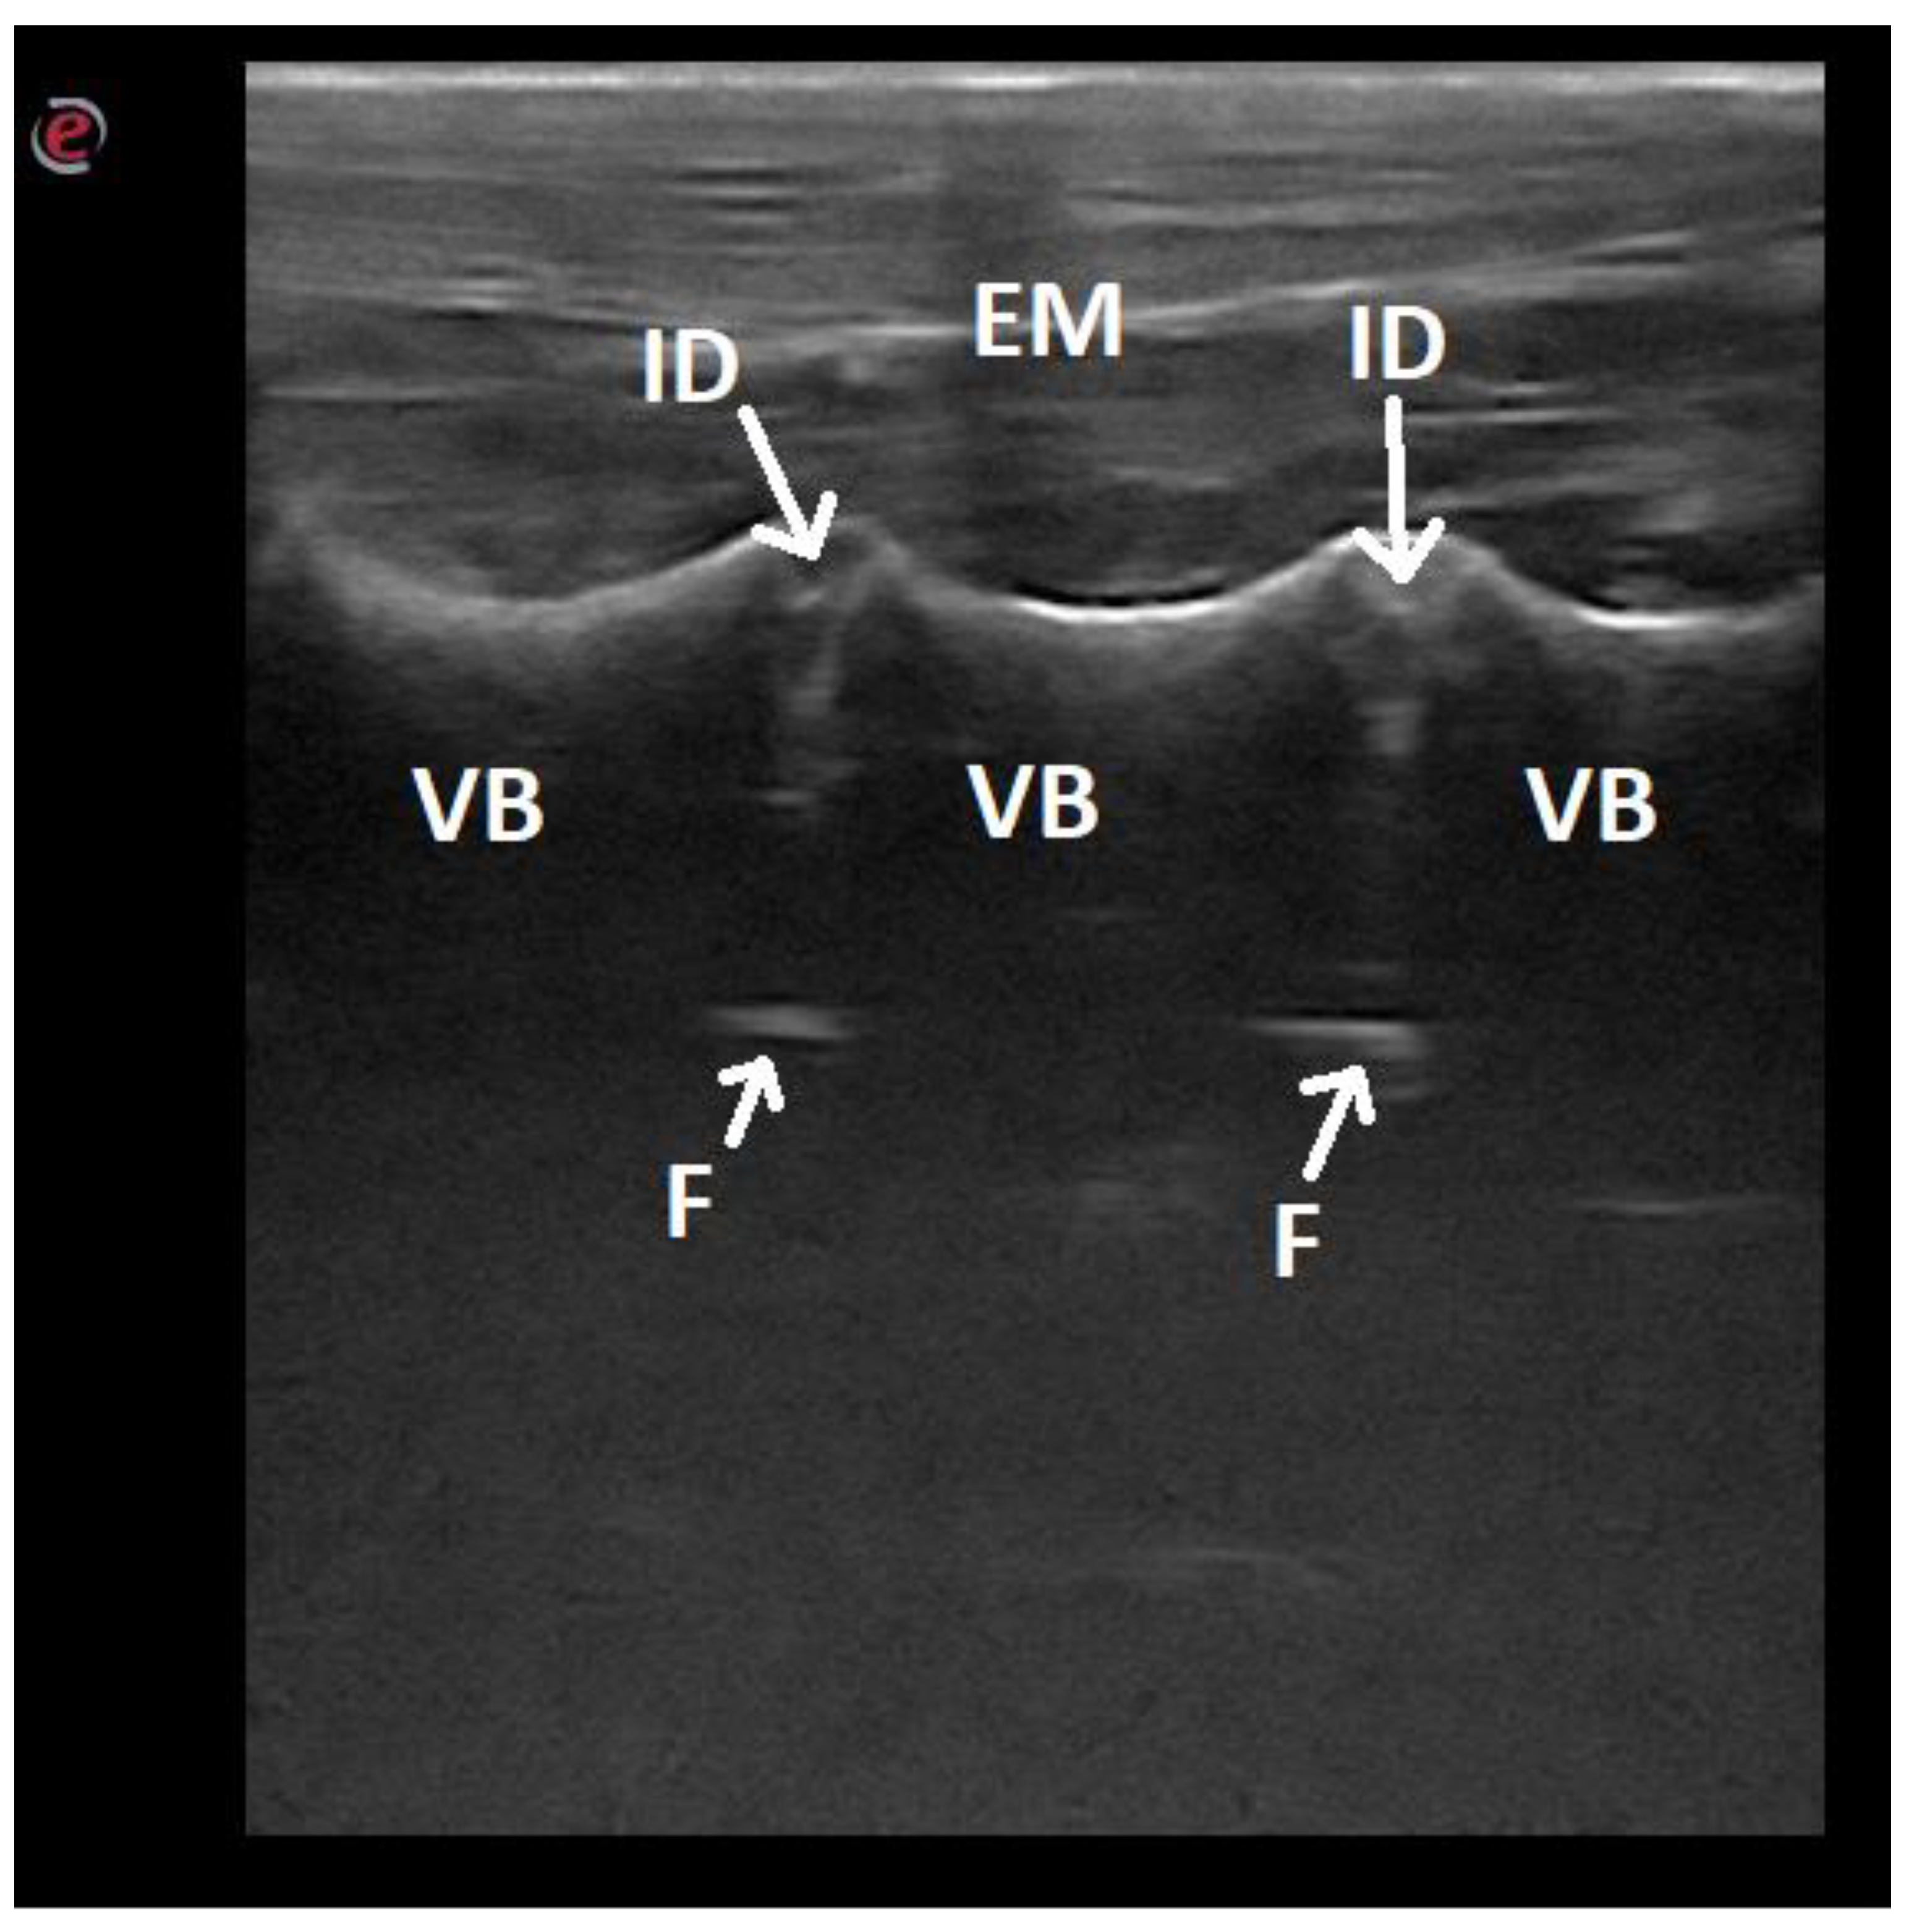

| Vertebral body | 23/100 |

| Intervertebral discs | 23/100 |